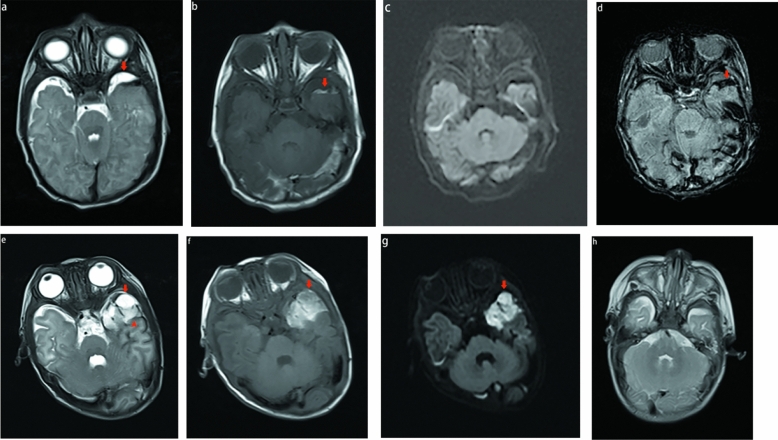

Six of the 34 patients had the first imaging pattern. Owing to different bleeding times, the signal performance of each sequence was different. Subpial meningeal hemorrhage may be either hyperintense or hypointense on T1 weighted and T2 weighted images. Only 2/6 showed restricted diffusion, and 2/6 subpial hemorrhages showed fluid–fluid levels. The different signals between the subpial hemorrhage and the subjacent cortical areas created a distinct MRI characteristic, characterized by the presence of dark or bright subpial bleed and normal cortical signals. Similar to previous studies, the mass effect and unique imaging feature of cortical inward depression (cortical buckling) created a yin-yang symbol8. Figure 1, particularly in T2WI and DWI. In this pattern, four patients had the yin-yang sign. Deep hemorrhage and cortex may be found with additional hypointense fluid on T2WI and DWI. The consistent presence of a bright, hyperintense subpial bleed, dark thin fluid layer, and an underlying normal cortex created another distinct MRI characteristic, resembling a sandwich sign (Fig. 1).

Figure 1.

MR images of 2 full-term neonates with pattern A. In the first patient (a–d), the subpial hemorrhage shows hepointense on T2WI (a), hyperintense on T1WI (b), no restricted diffusion (c), and hypointense signal on SWI (d). The combination of a dark or bright subpial hemorrhage collection and the normal underlying cerebral cortex forms a yin-yang symbol (a–b). In the second patient (e–g), the subpial hemorrhage shows hyperintense on T1WI and T2WI, with restricted diffusion (g). On T2WI (e), we found a thin layer of additional hypointense fluid in the deep aspect between hemorrhage and the cortex (arrowhead), the presence of a bright subpial bleed, a dark, thin layer of fluid and an underlying normal cortex-created sandwich sign. The first patient received MRI examination after 3 months; The subpial hemorrhage was completely absorbed and the cerebral sulcus fissure widened (h).